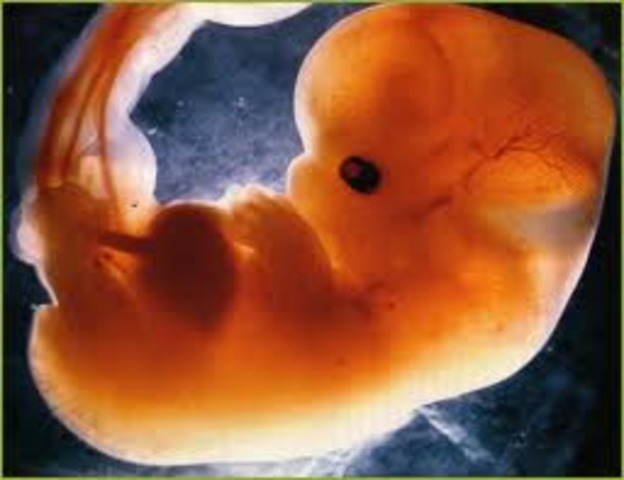

• PRIMER MES

PRIMER MES

*Al cabo del primer mes, el embrion ya posee los rudimentos de la boca, el tubo gastrointestinal y el higado.

*El corazon se empieza a desarrollar.

*El encefalo se empieza a diferenciar.

*El sistema nervioso comienza a formarse.

• SEGUNDO MES

SEGUNDO MES

*Se define la cara, la boca, los ojos, han aparecido los brazos y las piernas.